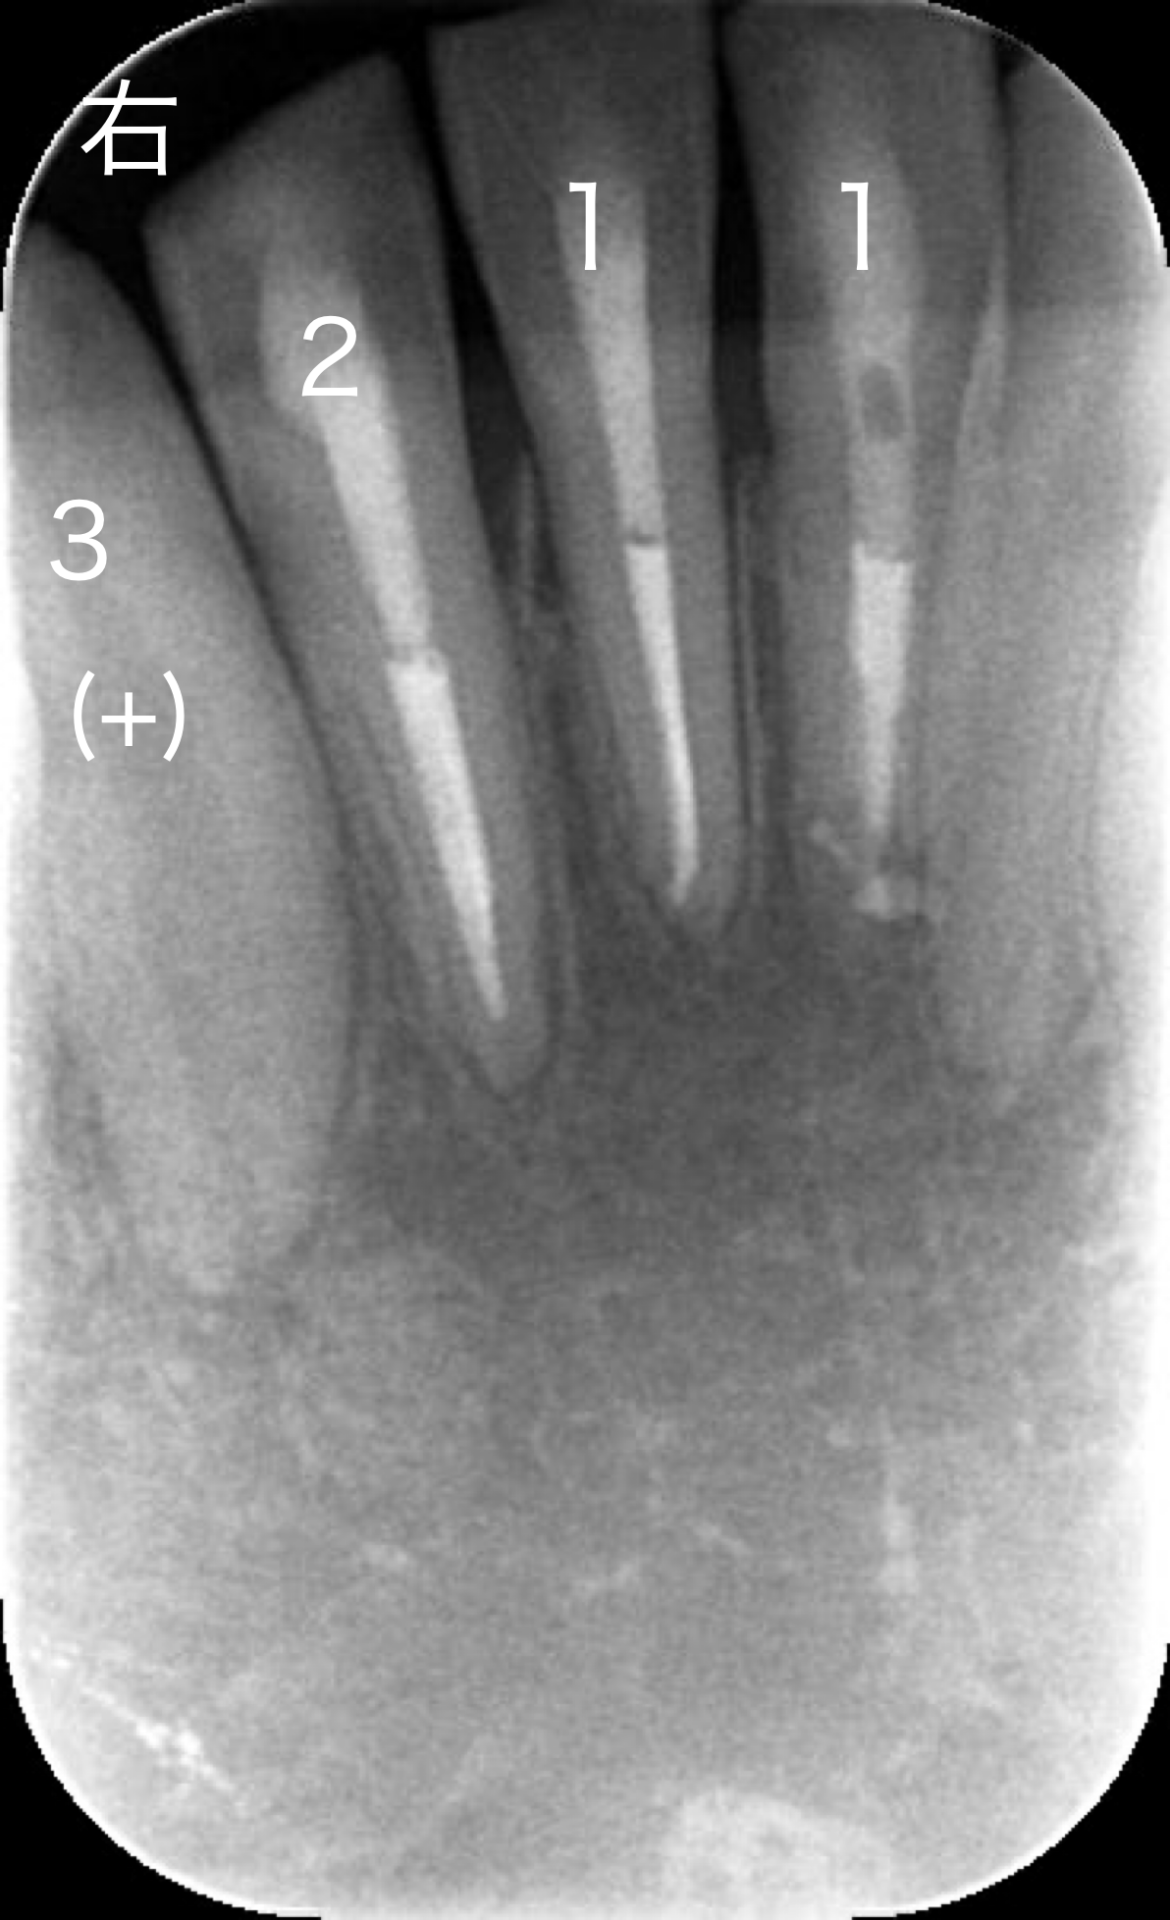

レントゲン画像です。下の歯の犬歯から犬歯の間を見ています。

両側の犬歯は成長過程で歯根がまだ完全に完成していません。

右下1,2番の根の先(根尖部)に僅かに透過像(影)があるように見えます。

*歯髄組織の反応あり/なしを(+)/(−)で表記しています。

・歯髄電気診断、冷温診いずれも反応を認めませんでした。